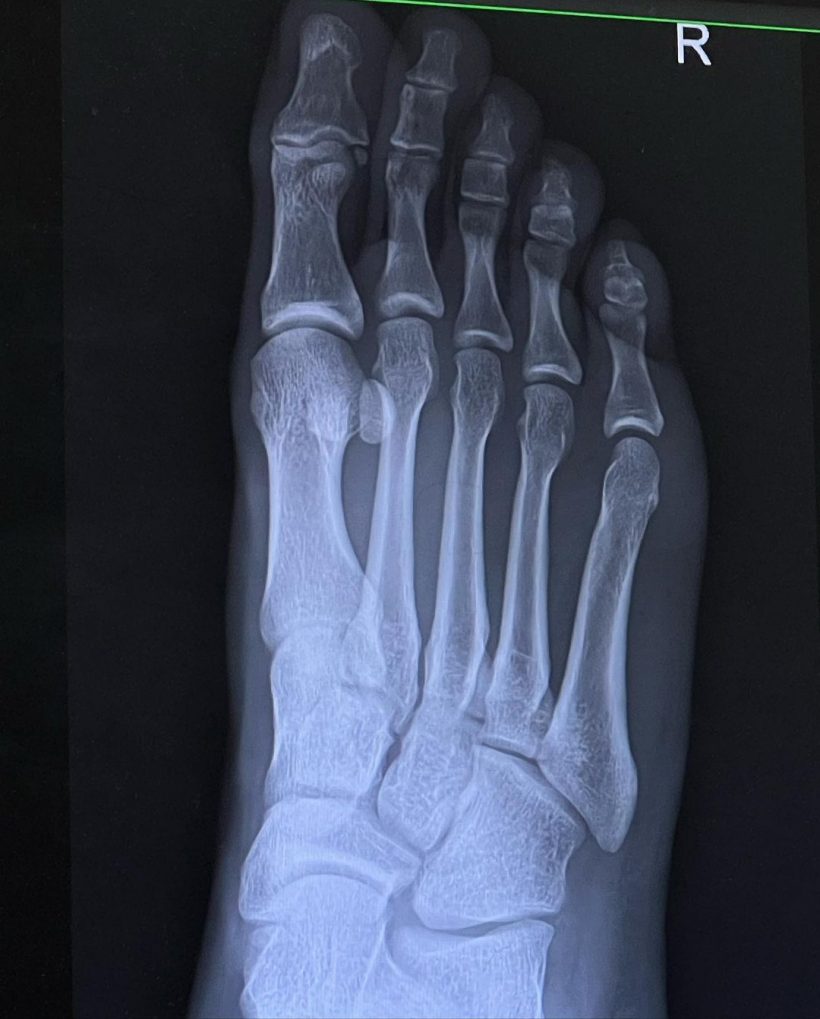

ล่าสุด ค่ำคืนที่ผ่านมา หนุ่มบอส ได้โพสต์ภาพพร้อมเเคปชั่นว่า “เรียบร้อย!! 2-1 🔴 เอ๊ย ผิดครับ!!! เหล็กทับ 👣 เต็มๆ เหล็ก 11 โล (เหล็กล้วนไม่มียางผสม) หลน จากระดับ หัวไหล่ เหลี่ยมลง เท้า เต็ม ๆ จากทรง คือ ดูไงไม่น่ารอด กระดูกน่าจะไม่หัก ก็ ต้อง ร้าว สรุป!! เอ็กซเรย์ ออกมา หมอ บอกเกิ๊นน ไม่เป็นอะไรเลย กระดูกปกติแข็งแรงมาก เอ็นไม่ขาด กล้ามเนื้อไม่ฉีกขาด #ขาผมอดาแมนเที่ยม 🦿เตือนทุกคนนะครับ ใส่รองเท้าทุกครั้งเวลาออกกำลังกายอะไรที่อันตราย หนักจะได้เบาลง ถ้าไม่มีรองเท้าถุงเท้า ผมว่าน่าจะหักละเอียดเลย GYM ไม่ใช่ของเล่นนะครับ 🦾🦿🧠 #เหมือนปีนี้มีแต่เรื่องซวยดีสุดในชีวิตมีแค่เรื่องเดียว“